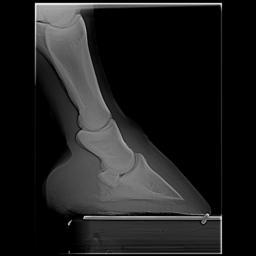

Posted on Thursday, Apr 5, 2007 - 1:11 pm: Dr O,I just read this article today after meeting with my vet and farrier yesterday regarding my horse's heel pain and I would like to get your input, if possible. I have had Remy for 6 years and have fought his low heel, long toe confirmation the whole time. In hindsight we did not do the right thing although we had the right idea. She said that if this had been managed properly for the past 6 years there would not be the damage there is now. I think the thing we missed was regular radiographs to see what was really going on. We just assumed that because he was not lame he was ok inside - the radiographs taken yesterday show that definitely was not the case. There is damage to the navicular, pedal osteitis, bone spurs and other things going on now. We have put him in 7 degree wedge pads with soft impression material. He walked off almost sound after the shoes were put on. I'm keeping a close eye on him because he can be sensitive to anything touching his sole as he has extremely thin soles. My vet said that it is important for sole growth that the frog had pressure - I had never heard that before. My vet said that it is possible that some healing can take place and he can return to regular work. She said that if the corrective shoeing doesn't work the next step would be injections - and she sounded pretty positive about the injections. We will continue to take regular xrays every 3 shoeings until we see the improvement we want. Does this sound like a good plan? I'm going to upload some radiographs that will give you an idea of what we are dealing with. I hope the thumbnails are large enough for you to view. I would greatly value any input you can give me. BTW I absolutely love this article! I'm going to print it and give it to my farrier. It's basically the same thing that he and my vet have said to me but it may have a couple extra insights. Thanks, Dawn Left front     Right front

Posted on Friday, Apr 6, 2007 - 6:36 am: Hello Dawn,I have moved your post into this new discussion. Using the radiographs as guides it would appear to me that the left could use around 7 degrees but the right a little less. This assumes the horse was standing square while radiographed. While radiographs are critical early in the assessment, because your feet do not appear to have any rotation of the coffin bone, you can assess proper balance without radiographs. This and how the foot responds to your work should be your guide to whether you have balanced these feet correctly. DrO |